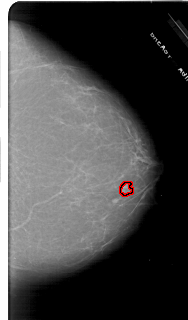

A_1716_1.RIGHT_MLO

RIGHT_MLO LINES 6496 PIXELS_PER_LINE 3586 BITS_PER_PIXEL 12 RESOLUTION 43.5 OVERLAY

FILE: A_1716_1.RIGHT_MLO.OVERLAY

TOTAL_ABNORMALITIES 1

ABNORMALITY 1

LESION_TYPE MASS SHAPE LOBULATED MARGINS MICROLOBULATED

ASSESSMENT 4

SUBTLETY 4

PATHOLOGY BENIGN

TOTAL_OUTLINES 1

BOUNDARY